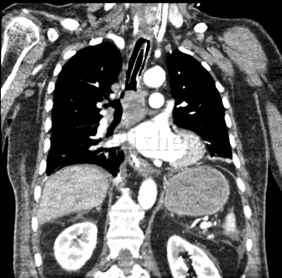

Neoplasia de carina principal